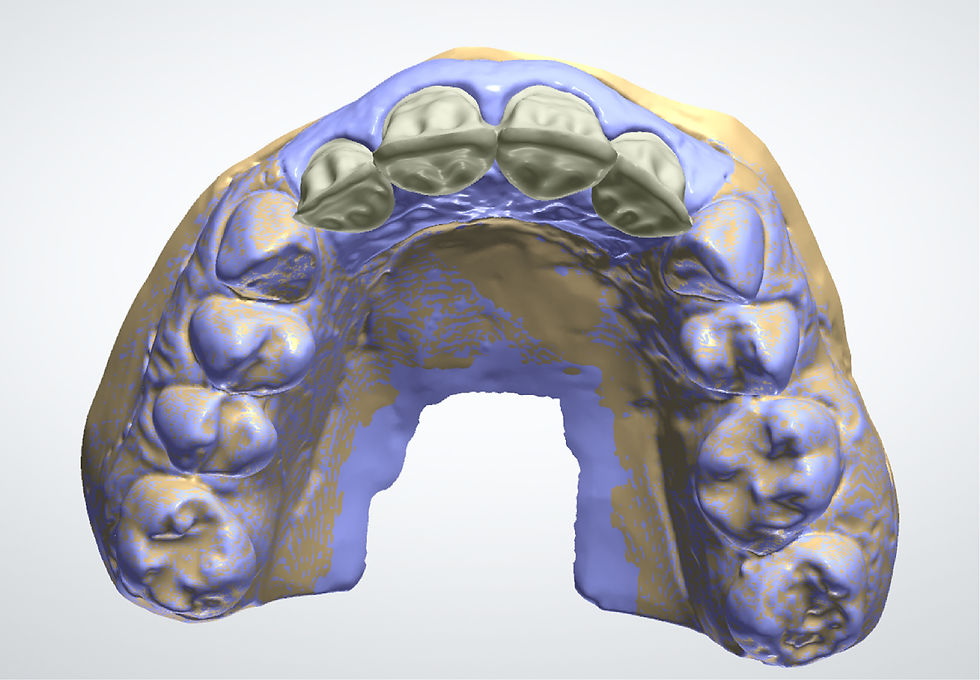

CAD-CAM planning of the definitive prosthesis.

Impression taking and model for the realization of the definitive prosthetic structure.